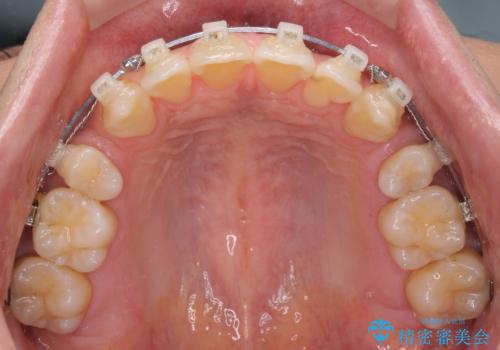

- クリアブラケット

- 口元の閉じにくさと、前歯のでこぼこの歯並びを気にして来院された患者様です。

口元を積極的に引っ込めるために、上下左右の小臼歯計4本を抜歯することとしました。